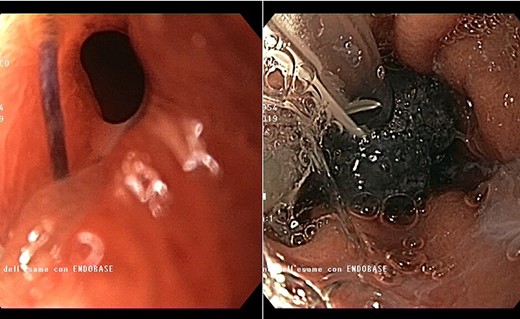

Intracavitary placement of E-VAC with prompt progressive improvement of the cavity size.

high PCR (291 mg/L) and the CT scan showed a right hydropneumothorax (Fig. 1). The first suspicion was an anastomotic leak and, in consideration of the hemodynamic instability and the severe septic state, the patient was submitted to emergency surgery. We performed a thoracoscopy with intraoperatively esophagogastroduodenoscopy which revealed a perforated prepyloric ulcer of the gastric tube. We therefore proceeded with accurate pleural toilette and closed the perforation with surgical stiches. At the end of the procedure, two thoracic drains and a naso-gastric tube with the distal end near the suture were placed. An additional naso-duodenum enteral feeding tube to ensure adequate nutrition was positioned. The patient was admitted in the Intensive Care Unit and supported with inotropic drugs, broad-spectrum antibiotics and proton pump inhibitor therapy. In the following days, the patient’s conditions improved allowing his extubation and his transfer to the surgical ward. Unfortunately, imaging and endoscopic check revealed a recurrent perforation. Considering the failure of the conservative approach, we decided to start the E-VAC Therapy on his 21st post-operative day (POD), using the Eso-SPONGE® System (B. Braun Surgical, S.A. Carretera De Terrassa, Rubi, Spain), firstly placed intraluminal because of the reduced size of the wall defect (Fig. 2). After three E-VAC replacements we did not observe any endoscopic or radiologic improvements. Moreover, on his 35th POD, due to a new impairment of vital signs, the patient underwent a second surgical treatment, with a new pleural toileting and another unsuccessful attempt of closing the conduit defect surgically. Considering the prolonged hospital stay, we placed a feeding jejunostomy. We proceeded with a new attempt of E-VAC, this time by placing it intracavitary (Fig. 3 and Fig. 4). The E-VAC was changed every 48–72 hours, reshaping the dimension of the sponge every time according to the size of the cavity. We observed a progressive reduction of the cavity size during the seriated endoscopic and CT evaluation. Considering the continuous improvement of patient’s clinical condition we discharged him after 84 days of hospitalization, with the E-VAC in place. The device replacement was carried on twice a week as an outpatient treatment, until its definitive removal (Fig. 5). The total duration of the therapy was 37 days with 13 E-VAC intracavitary interventions. Seven days after the device removal we performed an upper gastrointestinal X-Ray with oral contrast that showed no contrast medium leakage. The patient was therefore allowed to resume oral intake. At 6 months follow up the patient was in good clinical conditions; radiological test and endoscopy showed no abnormalities.